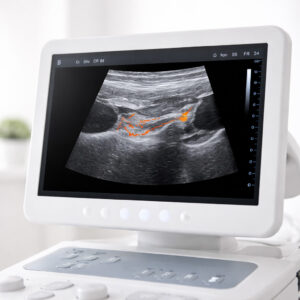

Die Ultraschalldiagnostik ermöglicht eine präzise Beurteilung der Halsweichteile und der Nasennebenhöhlen – schnell, schmerzfrei und ohne Strahlenbelastung.

Die Ultraschalldiagnostik (Sonographie) ist ein bildgebendes Verfahren, mit dem Strukturen im Hals- und Kopfbereich detailliert dargestellt werden können. Sie kommt ohne Röntgenstrahlen aus und liefert unmittelbar verwertbare Ergebnisse.

Mit der Sonographie lassen sich Lymphknoten, Speicheldrüsen, Schilddrüse sowie weitere Weichteilstrukturen differenziert beurteilen. Veränderungen können frühzeitig erkannt und in ihrer Ausdehnung eingeschätzt werden.

Ein Schallkopf wird auf die Haut aufgesetzt und die zu untersuchenden Bereiche werden in Echtzeit dargestellt. Der Ultraschall ist schmerzfrei, dauert nur wenige Minuten und erfordert keine besondere Vorbereitung.